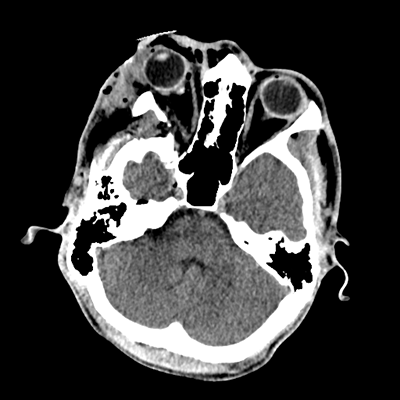

Initial vitals are notable for BP 111/67, HR 119, SpO2 100%, T 37.8C. She undergoes a whole-body CT scan. Trauma surgery also evaluates her. She has a zygomaticomaxillary complex fracture, comminuted fracture of her humerus, and fractures of ribs 2-6. Her non-contrast head CT is shown below. Plastic surgery evaluates her and recommends non-emergent operative repair of her facial fracture.

The patient has sustained multicompartmental hemorrhages—small amounts in the parenchymal, subarachnoid (mainly right frontal), subdural (right frontal, anterior temporal in particular), and intraventricular (layering in the right occipital horn) spaces. It’s a more subtle finding, but you can also see that the right hemispheric convexity has less sulcation, suggestive of cerebral edema on that side. There’s the right frontal contusion with hemorrhage there. There are also two small IPHs, in the right thalamus and left internal capsule. What do these represent? Likely diffuse axonal injury (DAI).